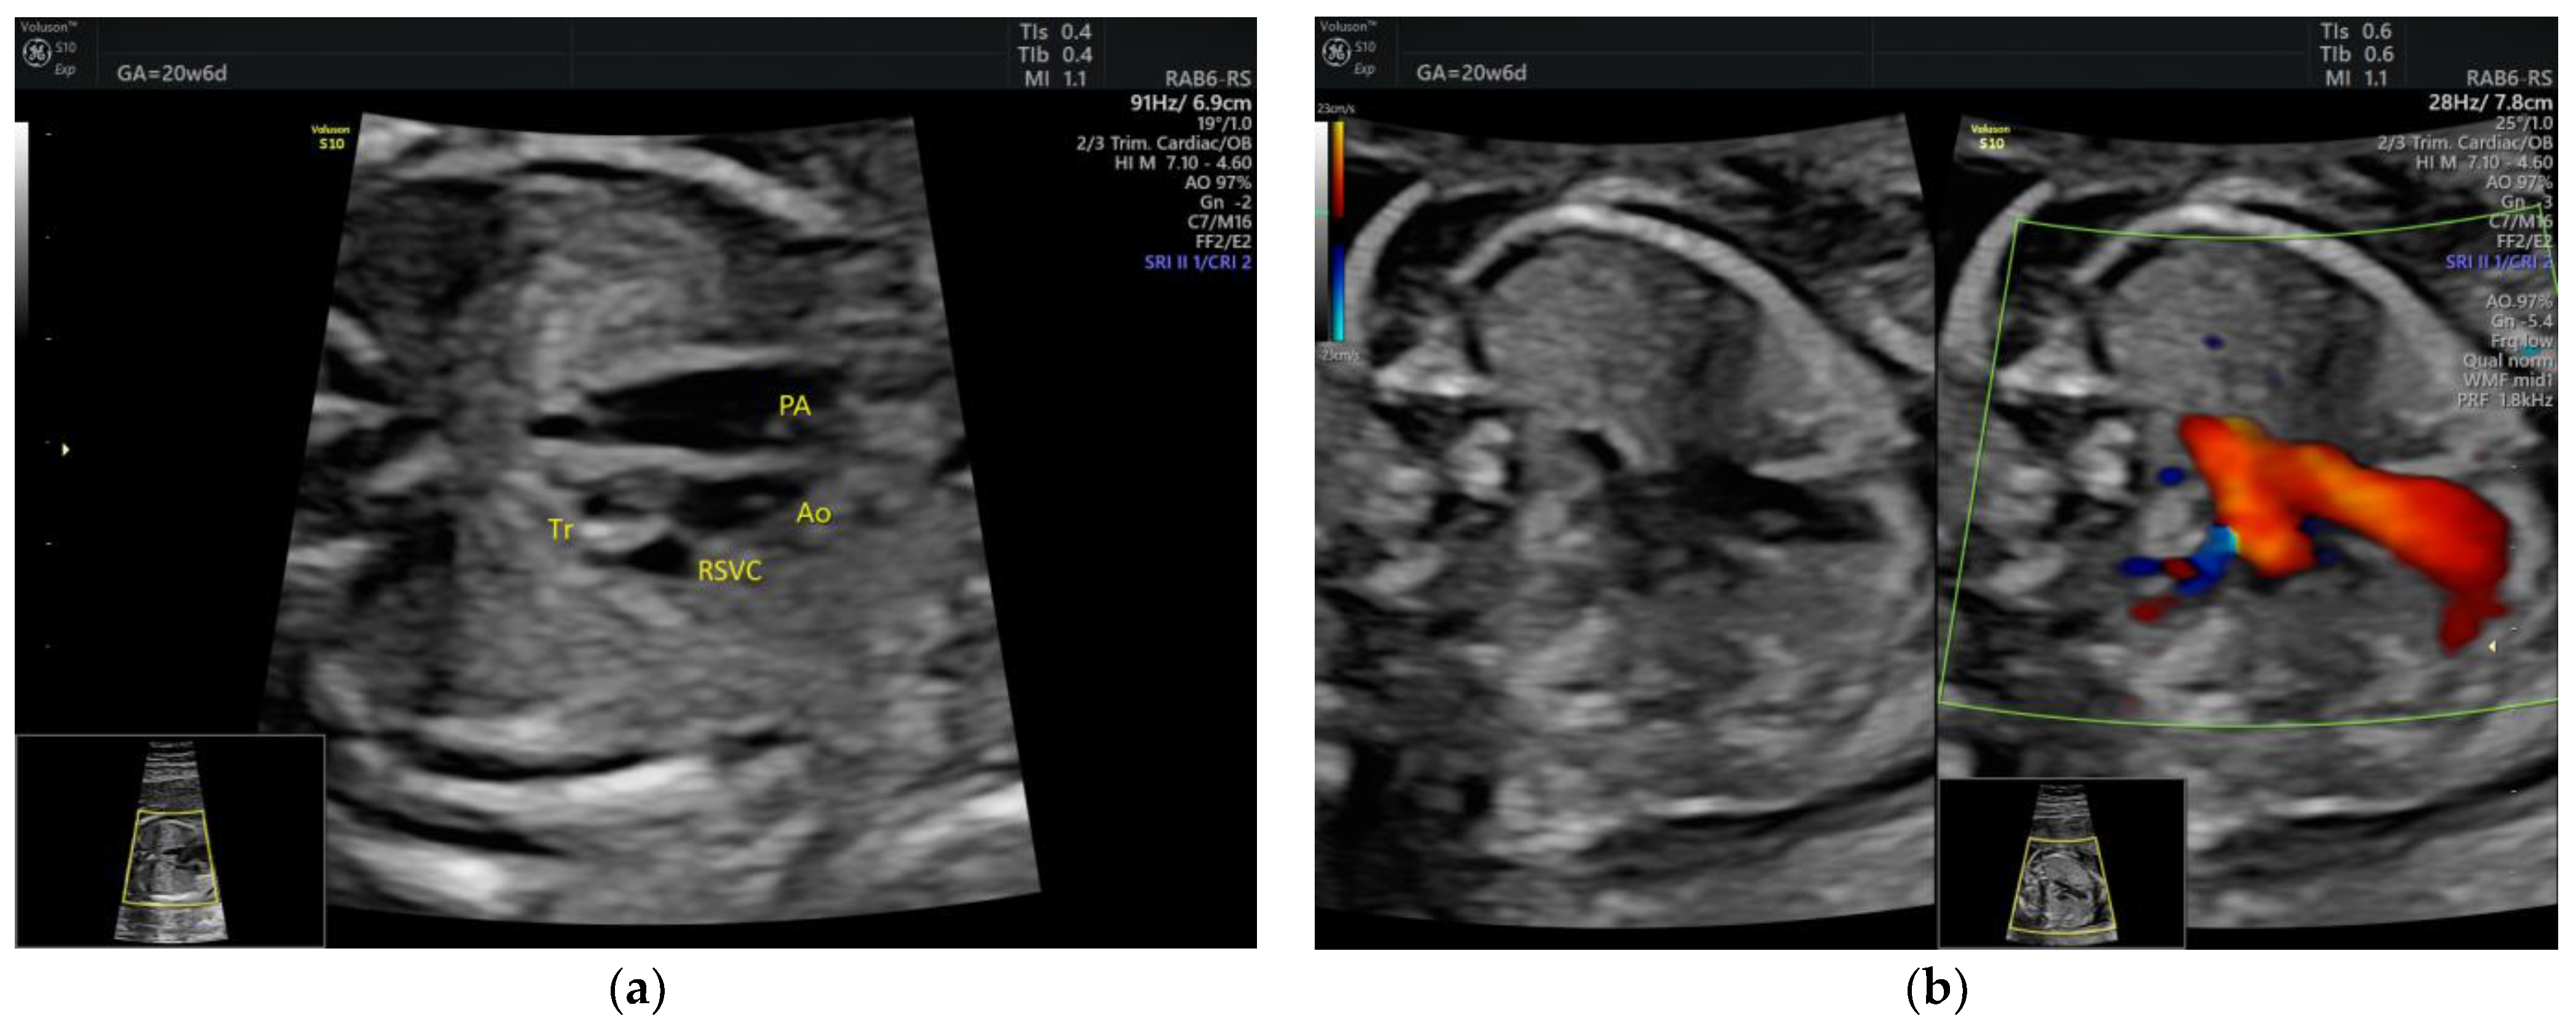

| Isolated ARSA | 6 | - | - | 3VT color | - | 0 | 6 | 0 | 2/5 |

| PLSVC | 4 | - | - | 3VT color | + | 0 | 4 | 0 | 4/4 |

| Intrathymic LBCV | 3 | - | - | 3VT color | - | 0 | 3 | 0 | 3/3 |

| DAA | 1 | Tortuous DA at 20 w + late FGR | - | 3VT | + | 0 | 0 | 1 | 1/1 |